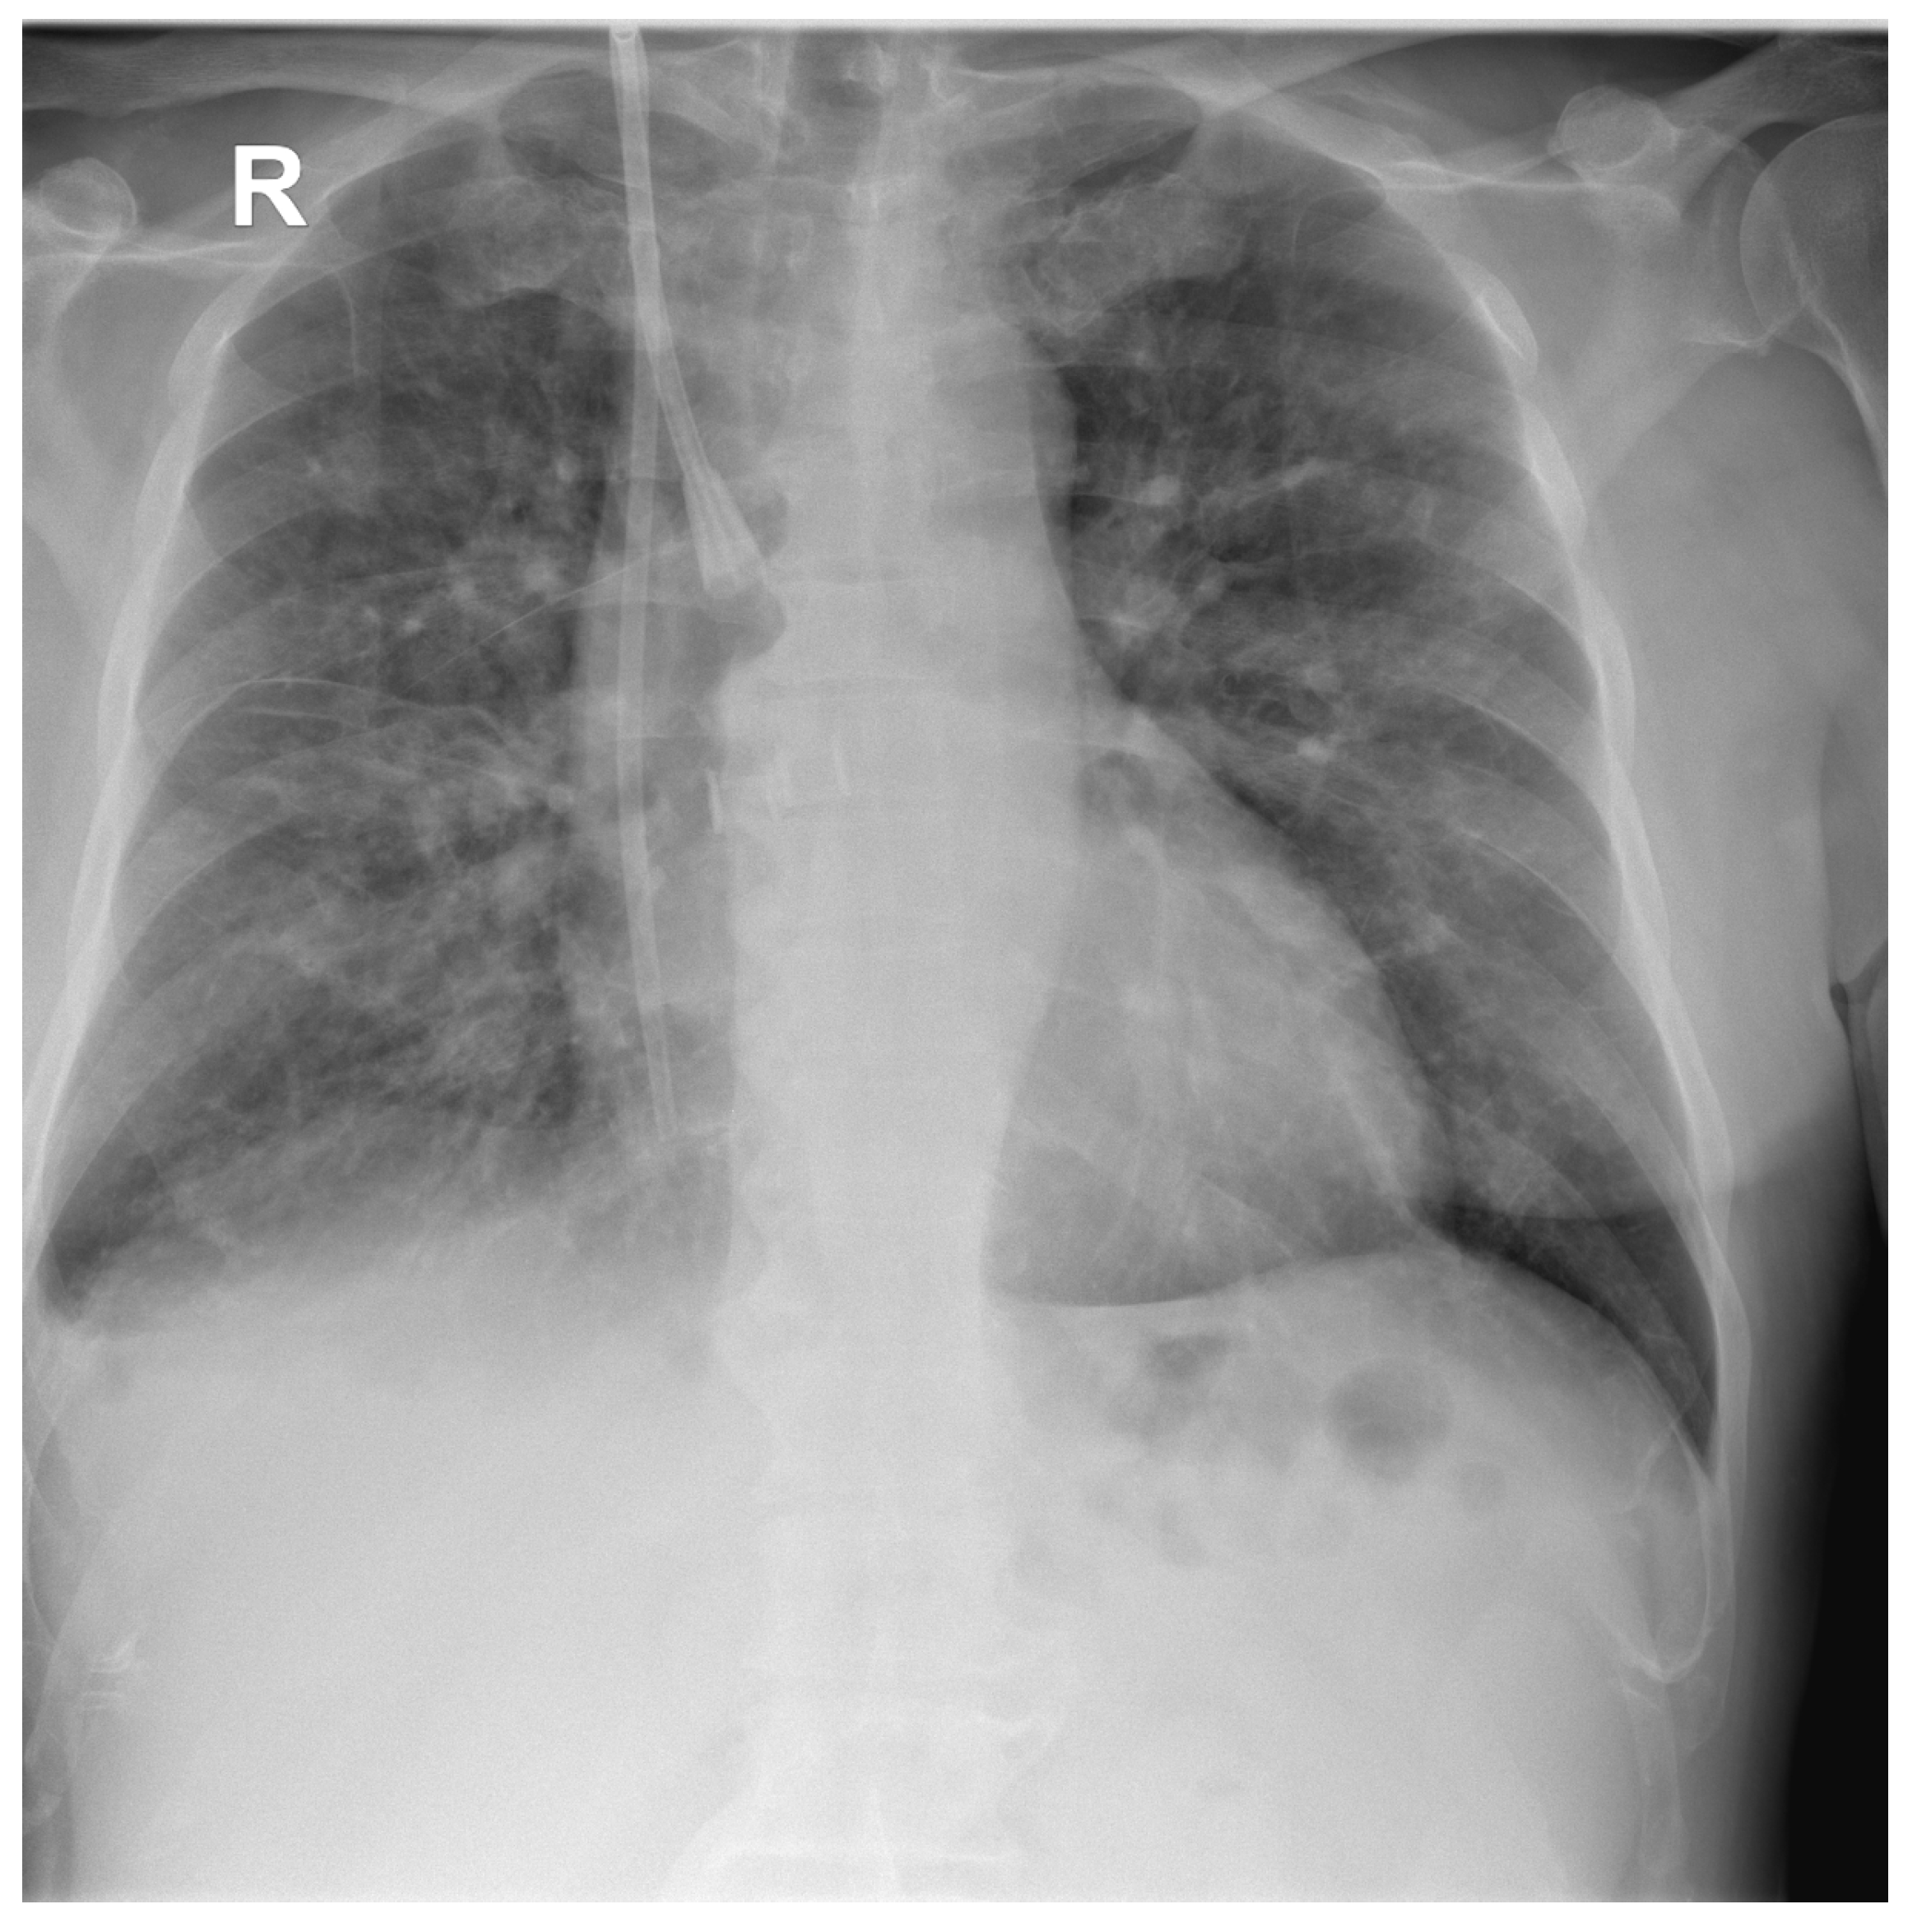

2.1. Case Report 1